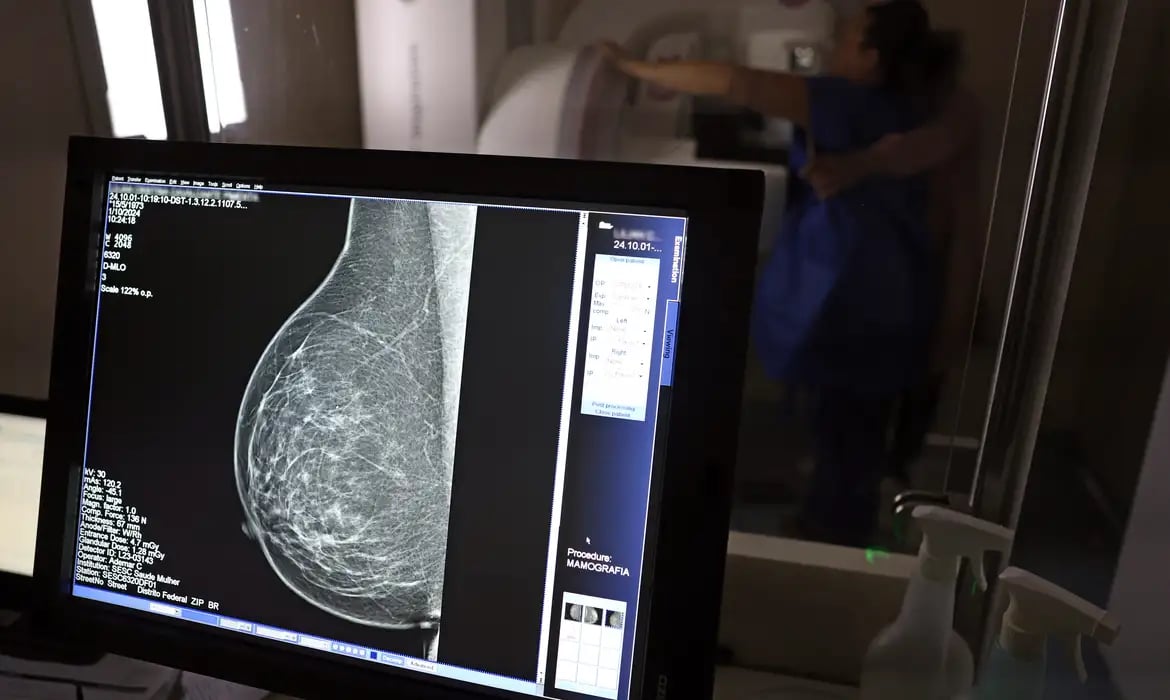

Falta de acesso a mamógrafos limita prevenção do câncer de mama

No mês de conscientização sobre o câncer de mama, um relatório destaca a importância de acesso igualitário ao rastreamento e tratamento da doença. Segundo o Atlas da Radiologia no Brasil, do Colégio Brasileiro de Radiologia e Diagnóstico por Imagem (CBR), o acesso aos mamógrafos ainda é um desafio.![]()

O país tem 6.826 equipamentos registrados, sendo 96% em funcionamento. Metade deles está disponível no Sistema Único de Saúde (SUS), responsável por atender 75% da população. Isso equivale a 2,13 mamógrafos por 100 mil habitantes dependentes do SUS.

Na saúde suplementar, que cobre 25% da população, o cenário é mais favorável: 6,54 aparelhos por 100 mil beneficiárias, quase o triplo da rede pública. O Acre exemplifica essa disparidade — são 35,38 mamógrafos por 100 mil habitantes na rede privada, contra 0,84 no SUS.

Há disparidades regionais. Roraima tem a menor proporção (1,53 por 100 mil), seguida do Ceará (2,23) e Pará (2,25). A Paraíba lidera o ranking (4,32), à frente do Distrito Federal (4,26) e do Rio de Janeiro (3,93).

O Brasil tem uma cobertura muito baixa de mamografias: 24%. O ideal recomendado pela Organização Mundial da Saúde é de 70%. Mesmo em lugares como o estado de São Paulo, que tem a maior concentração de mamógrafos do país, a taxa gira em torno de 26%.

Em setembro, o Ministério da Saúde ampliou as diretrizes de rastreamento, recomendando que mulheres entre 40 e 49 anos realizem mamografias, mesmo sem sintomas. De acordo com o Instituto Nacional do Câncer (Imca), mais de 73 mil mulheres recebem o diagnóstico de câncer de mama anualmente no Brasil.